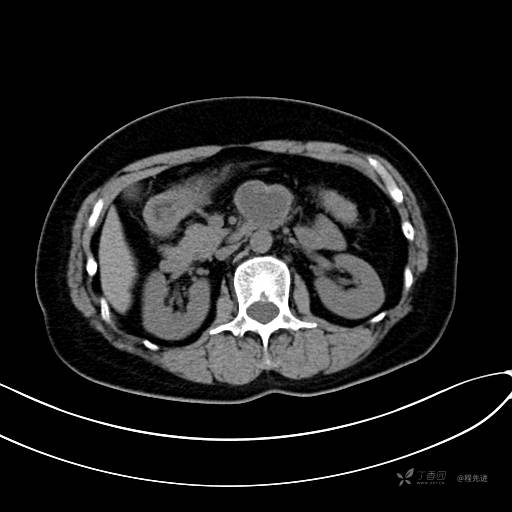

CT平扫